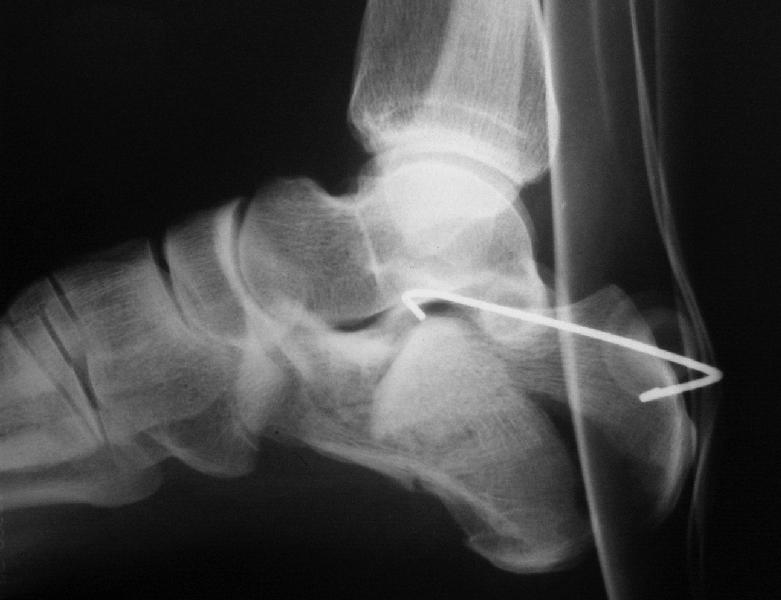

представляю снимки пациента с переломом пяточной кости. послеоперационный снимок этапный - по снятии швов спицы удаляю и наладываю циркулярную гипсовую повязку. к сожалению снимки с удаленной скобой представить не могу но поверьте на слово - консолидация полная, коррекция стойкая.

при планировании операции и ее исполнении выполнена костная аутопластика трансплантатом с гребня подвздошной кости причем трансплантат брался фрезой размером несколько болишим чем образованный в результате травмы дефект. скоба в данном случае обеспечивает компрессию между отломками-трансплантатом